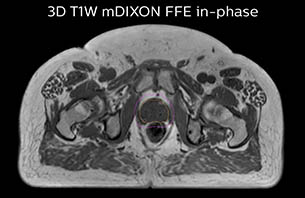

Using the mDIXON and 3D bFFE images, the RT planner marks the position of the nickel-titanium fiducial markers, and contours are transferred to the digitally reconstructed radiographs (DRRs). Reference image matching is based on these markers. “In the rare cases, where visualization of the fiducial markers fails, we do a CT to confirm their location,” Dr. Keyriläinen notes.

MR-only simulation workflow The 3D T1W FFE mDIXON sequence provides in-phase, water and fat images in one acquisition. Target and organs-at-risk are delineated on the 3D T2W TSE images. Prostate GTV is shown in orange, PTV in purple. The 3D bFFE sequence is used by the planner to mark the position of the fiducial markers (gold anchors) and contours are transferred to the digitally reconstructed radiographs (DRRs).

Based on the 3D T1W mDIXON images, MR-based density maps (MRCAT) are automatically generated. The VMAT (Volumetric Modulated Arc Therapy) plan is generated in TPS, based on MRCAT as primary image set. During the commissioning phase, dosimetric agreement between MRCAT-based and CT-based dose plans was studied and differences in the PTV dose were found to be minimal (<1% for most patients). Average difference in PTV mean values was 0.8% over the study group (n=62).